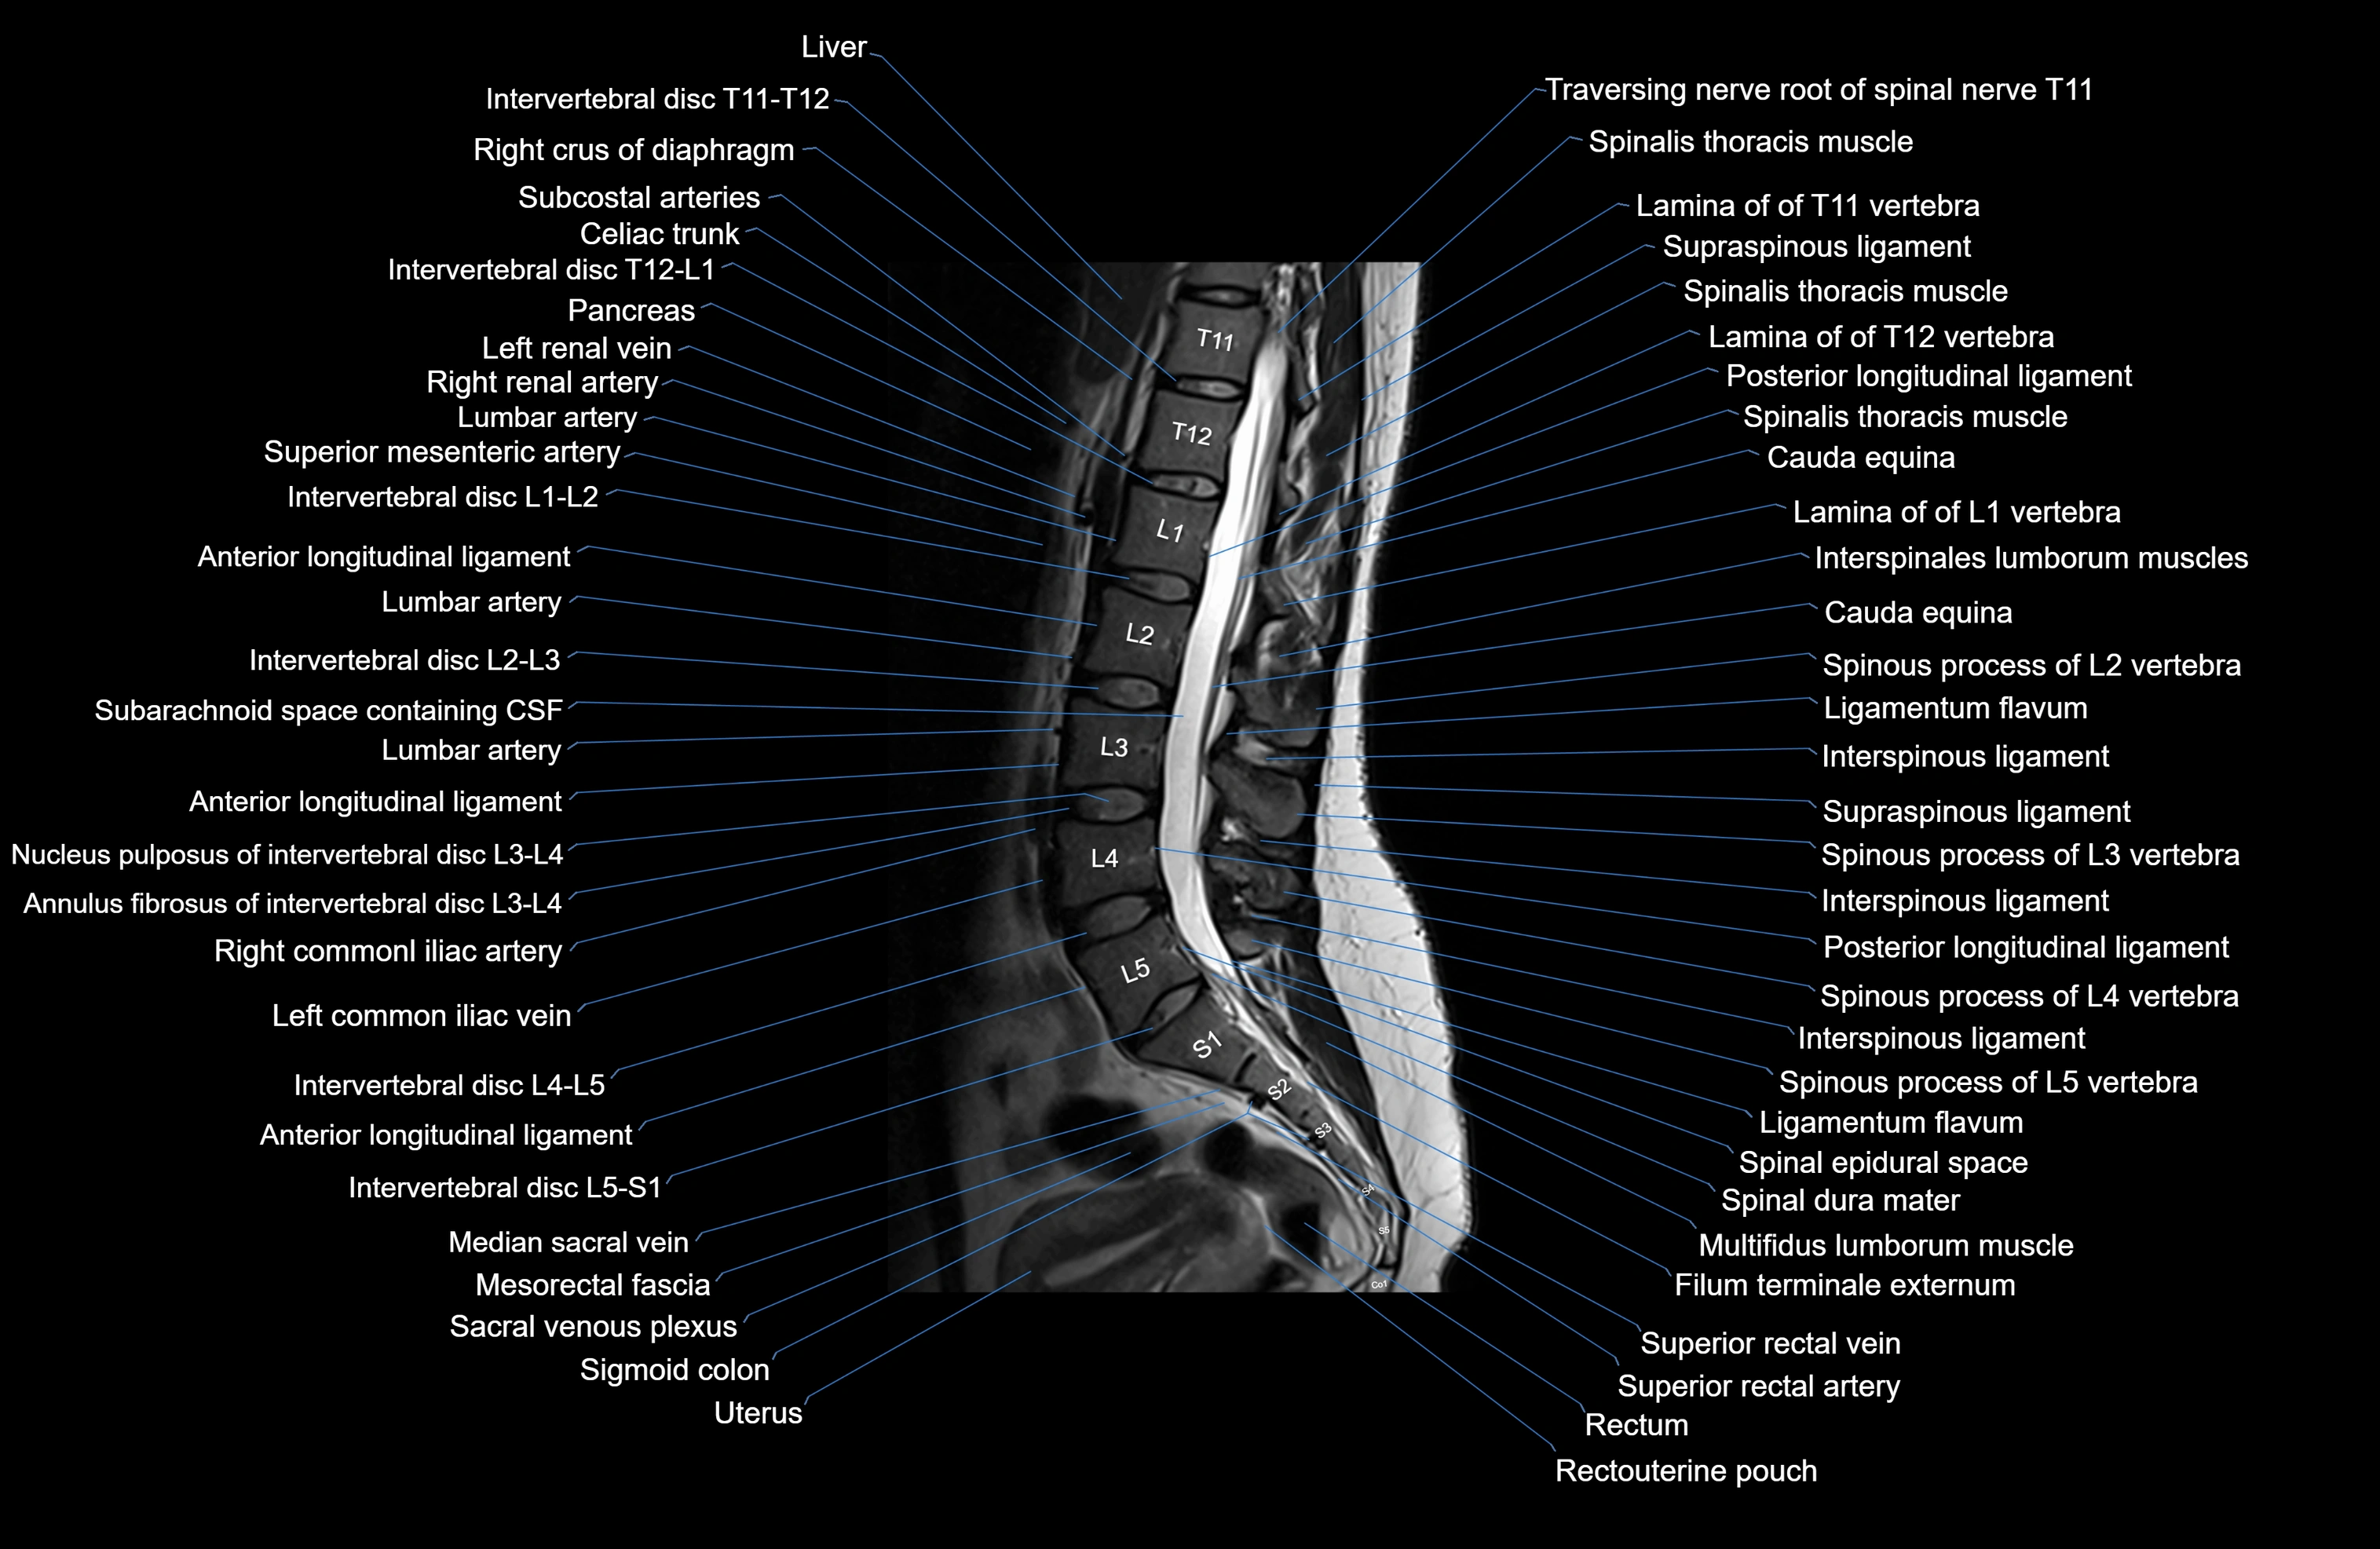

MRI images